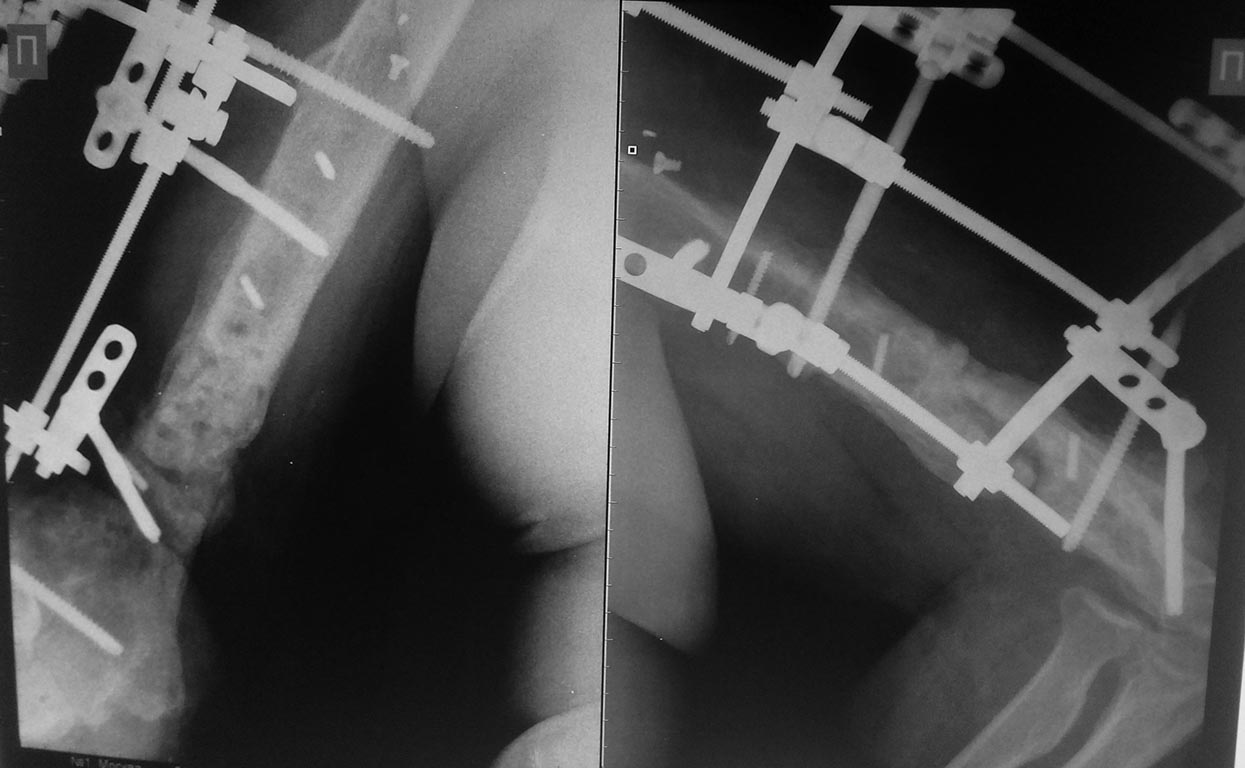

5 месяцев с АВФ

5 месяцев с АВФ боковая